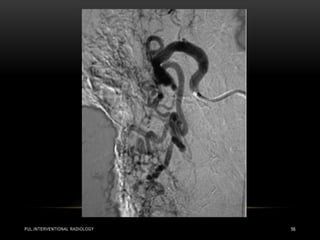

• During embolization, the supplying artery immediately preceding

the PAVM is the target to occlude the feeding vessel just

proximal to the aneurysmal sac .

• The deployed coils are designed to coil within the vessel lumen

and carry micro fibers that activate platelets to generate an

occluding platelet plug.

• Amplatzer vascular plugs (AVPs) and balloon devices provide

direct obstruction to vascular flow.